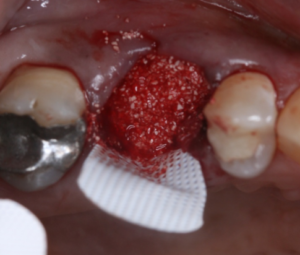

Vista oclusal do alvéolo preenchido pelo enxerto Extra Graft e membrana em posição.